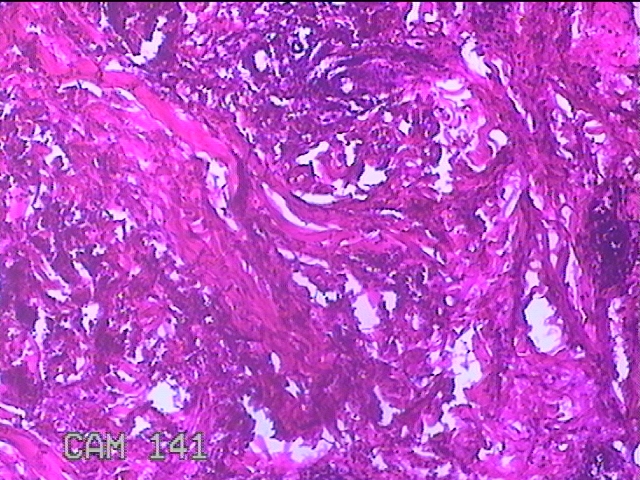

性别

女

年龄

39岁

临床诊断

皮下结节

一般病史

发现左臀部多发性结节5年余。

标本名称

左臀部结节

大体所见

灰白粉红色结节0.7x0.3x0.2cm一个,表面糜烂。

图3